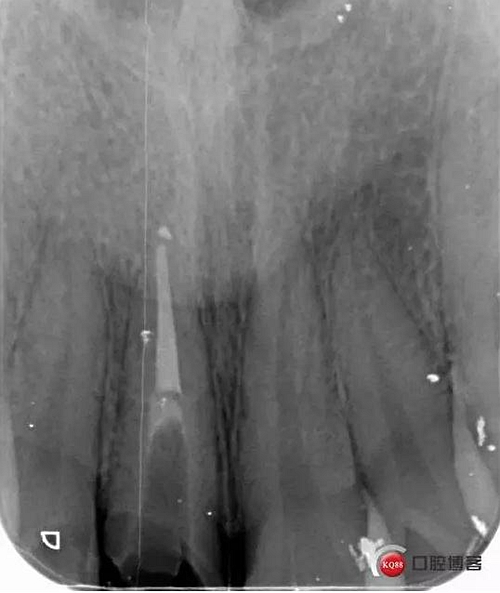

看起來有點頭痛哈,拍片檢查

牙根長度比較號,根充完善。這張片子也可以看出,為什么上次脫落了,樁的深度不夠,而且明顯樁根樁道不匹配,打的樁都沒有到位。